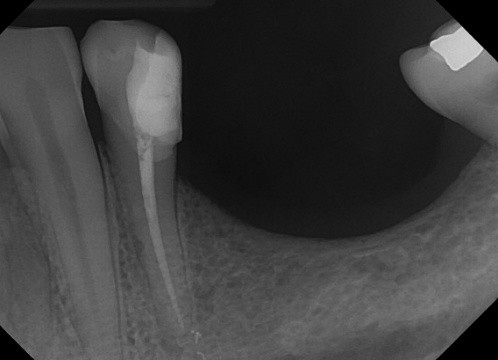

3 / 50

3. (Select ONE OR MORE correct answers)

The radiograph shows evidence of calculus on

4 / 50

4. (Select ONE OR MORE correct answers)